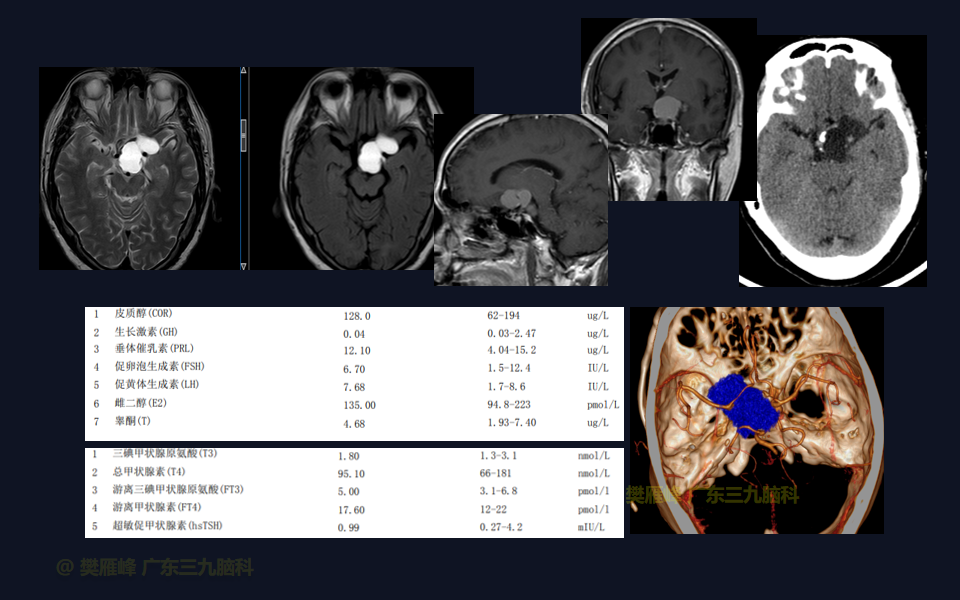

在这个二维手术视频中,展示了一种经翼点入路颅咽管瘤。患者是一名50岁的男性,有1月的左眼视物模糊、无多饮多尿病史,神经影像学显示鞍上区-桥前池示一团块状短T1长T2,Flair序列高信号,分叶状,边缘轻度线样强化,大小约47.5×33×33mm,邻近左侧颈内动脉-大脑前、中动脉局部受包绕的鞍上的颅咽管瘤。经术前讨论选择经扩大翼点入路颅咽管瘤切除,以实现肿瘤全切除,保护周围神经血管。术后术后尿量增多,10天后好转;视力、视野同术前改变;神经影像学显示肿瘤全部切除。我们展示了安全的神经血管保护和肿瘤切除术的细微差别和技术要点,以及手术技术。